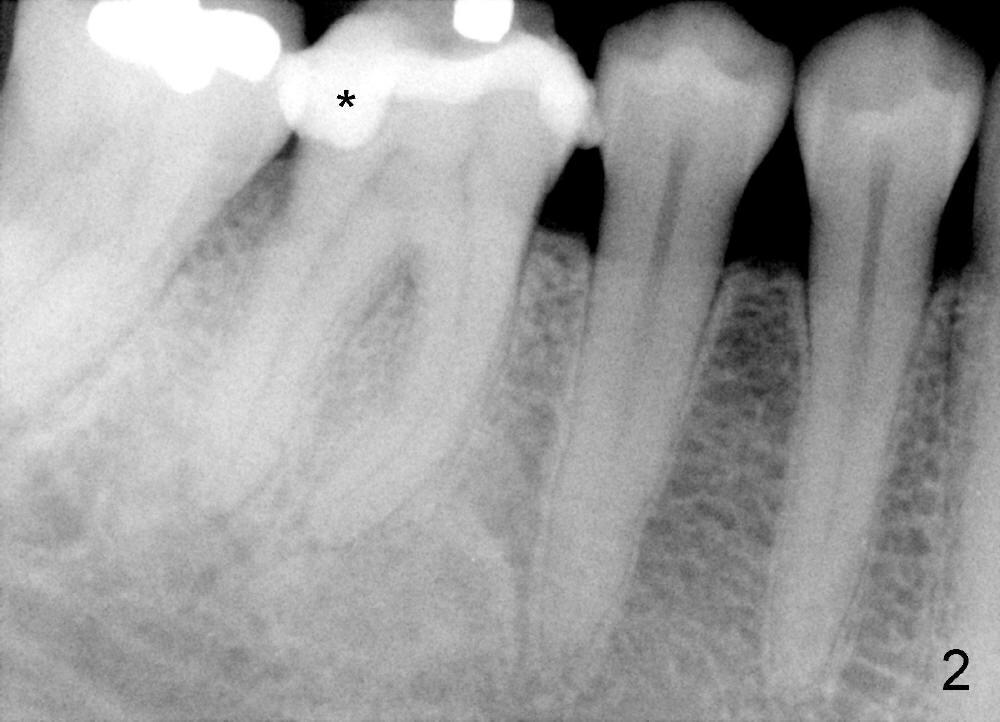

Dowman太太来自德国,收入不好,抽烟,不用牙线,结石多(图一箭头),右下第一磨牙远中龋齿(*)。她深洗还积极(图二已经没有明显结石),处理龋齿拖拖拉拉,九个月后,去龋时穿髓,暂封(图二*),她的后牙牙根特长,说明什么?下面回答。不得不做根管治疗(图三),图四是根管治疗后一年半拍摄,虽然根尖有阴影(箭头),但是病人没有任何症状。又过两年多病人主诉右下不适,根尖片显示根分叉阴影特大(图五*),近中根近中也有阴影(箭头),这时结石又出现。口内检查太容易了:右下第一磨牙颊侧有瘘道(图六双箭头),颊侧根分叉上皮附着失去(图六单箭头,也就是牙周袋深,探测出血),而舌侧根分叉牙周袋正常。总之,近中根有隐裂,接近颊侧,而远中根好像不容易出事,因为它比近中根粗。当我们为她牙齿惋惜时,老外比较爽快,说“It is not your fault. I love eating nuts. I grind my teeth at night. My night guard is too old to wear”。这段话可能说明为什么她后牙牙根长。